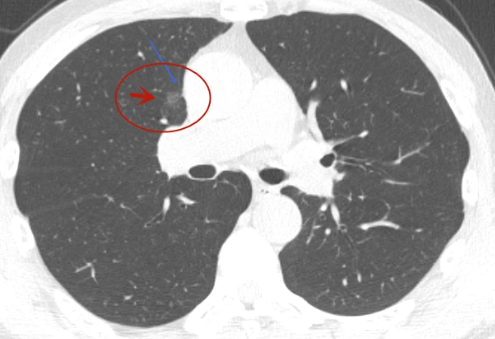

肺磨玻璃结节的特点就在于“磨玻璃”。专业来讲,“磨玻璃”就是病灶密度不足以掩盖肺内走行的血管和支气管影;通俗来讲,“磨玻璃”就是状似磨玻璃的“虚影”。这些“虚影”又可分为“一点实影也没有”的纯磨玻璃结节和“虚实混杂”的混杂性结节,其中,混杂性结节又称为部分实性结节。

既然肺磨玻璃结节的病因有“良”有“恶”,那什么模样的结节恶性程度的可能性较高呢?恶性程度较高的肺磨玻璃结节通常具有以下特点:

逐渐出现实性成分或实性成分逐渐增加;

呈分叶状或有毛刺。